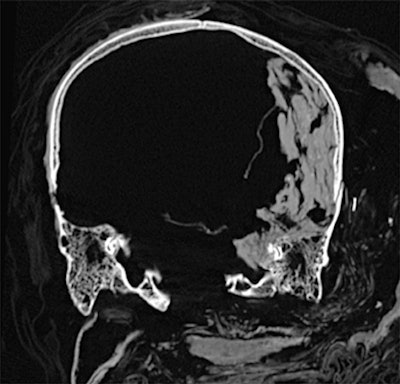

Dr. Sahar Saleem, a professor of radiology at Cairo University who specializes in CT mummy imaging, and archeologist Zahi Hawass, PhD, have used CT scans and 3D reconstructions to suggest he had multiple killers. They have presented their findings in an article published on 17 February in Frontiers of Medicine that received over 10,500 page views by 21 February.

CT revealed details of the head injuries, including wounds that had not been discovered in previous examinations and had been skillfully hidden by the embalmers. The mummy's deformed hands indicate that Seqenenre may have been captured on the battlefield, and his hands were tied behind his back, preventing him from deflecting the fierce attack on his head.

The CT scans, combined with other evidence, suggest the execution was carried out by multiple attackers, which the scientists confirmed by studying five different Hyksos weapons that matched the king's wounds. The study also determined that Seqenenre was about 40 when he died, based on the detailed morphology revealed in the images, providing the most precise estimate to date, according to the authors.

In addition, the investigation revealed details about the mummification of Seqenenre's body. For instance, the embalmers used a sophisticated method to hide the king's head wounds under a layer of embalming material that functioned similarly to the fillers used in modern plastic surgery. This would imply that mummification took place in a real mummification laboratory rather than in a poorly equipped place, as previously interpreted.